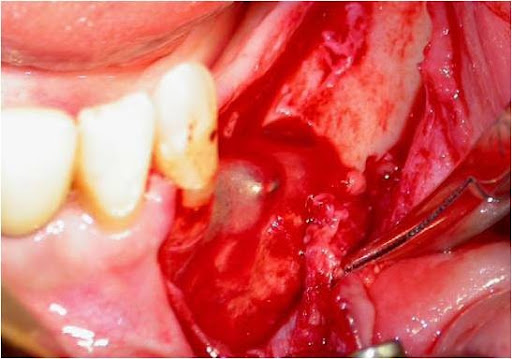

A incisão deve ser linear sobre a crista alveolar, iniciada no trígono retromolar e, com pequeno desvio para lingual, segue em direção à região do canino, sendo acompanhada de uma extensão no rebordo alveolar vestibular anterior ao canino, como forma de garantir um retalho que irá cobrir todo o defeito ósseo, protegendo-o de fenestrações ou de infecções. Uma vez descolado o retalho localiza-se o forame mentoniano e libera-se com extremo cuidado o periósteo do feixe no nervo mentoniano (Fig. 4).

Fig. 4 - Após a incisão o retalho totalmente afastado, mostrando o forame mentoniano já perfeitamente liberado do periósteo.